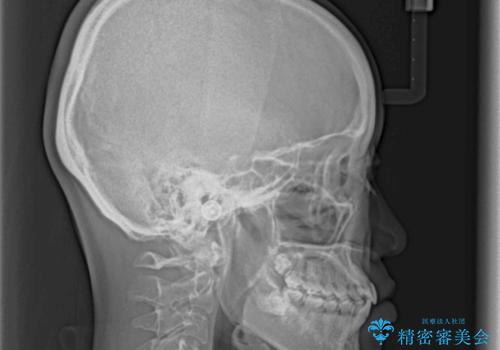

上下の奥歯を圧下させるようにすることで、前歯を接触させるように計画しました。

隙間に舌が入り込むことが話しにくさに繋がっていたため、舌の筋肉のトレーニングも並行して行い、話しにくさの改善と後戻りの抑制を図りました。